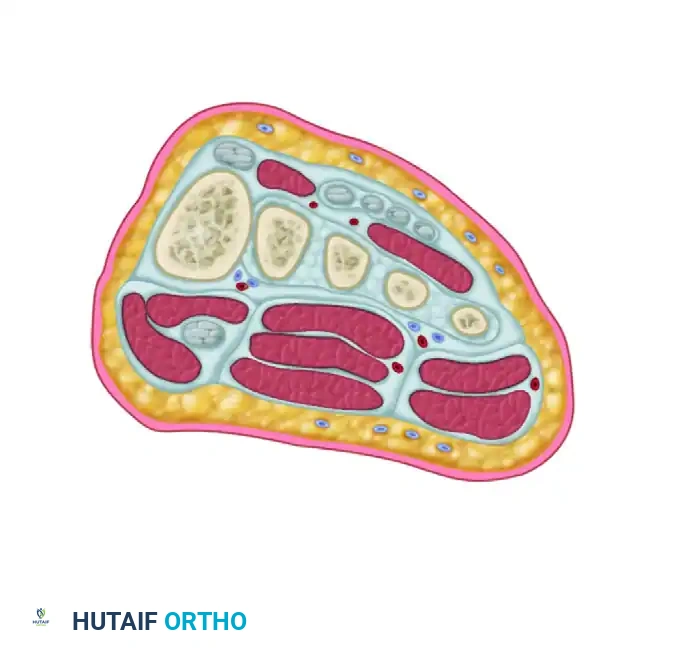

Anatomy and Biomechanics

The stability of the tarsometatarsal (TMT) joint complex relies on both its intrinsic bony architecture and a robust ligamentous network. The base of the second metatarsal is recessed proximally between the medial and lateral cuneiforms, creating a "keystone" configuration that locks the midfoot.

Crucially, there is no transverse ligament connecting the bases of the first and second metatarsals. The primary stabilizing structure is the Lisfranc ligament, a thick, oblique interosseous band originating from the lateral aspect of the medial cuneiform and inserting onto the medial base of the second metatarsal. Disruption of this ligament, either through direct crush injuries or indirect axial loading on a plantarflexed foot, leads to catastrophic destabilization of the medial column.